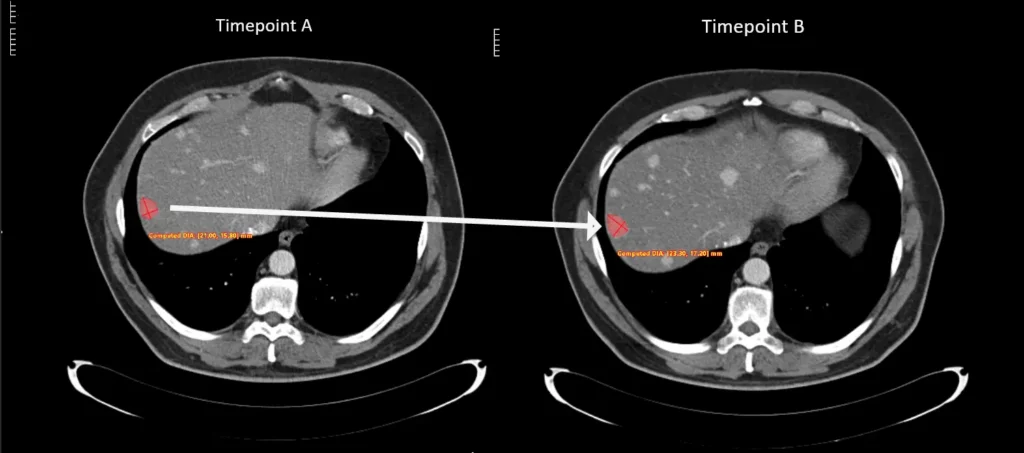

Voiant Hub 2.0 streamlines segmentation and tracking for semi-automated RECIST and volumetric automated RANO assessments, enhancing accuracy, consistency, and compliance in tumor response and tumor burden evaluation.

RECIST and RANO spider plots offer comprehensive insights into drug efficacy by clearly evaluating patient responses to treatments.

These interactive tools visually track lesion changes across multiple timepoints, offering a clear, longitudinal view of disease progression and treatment response over time.